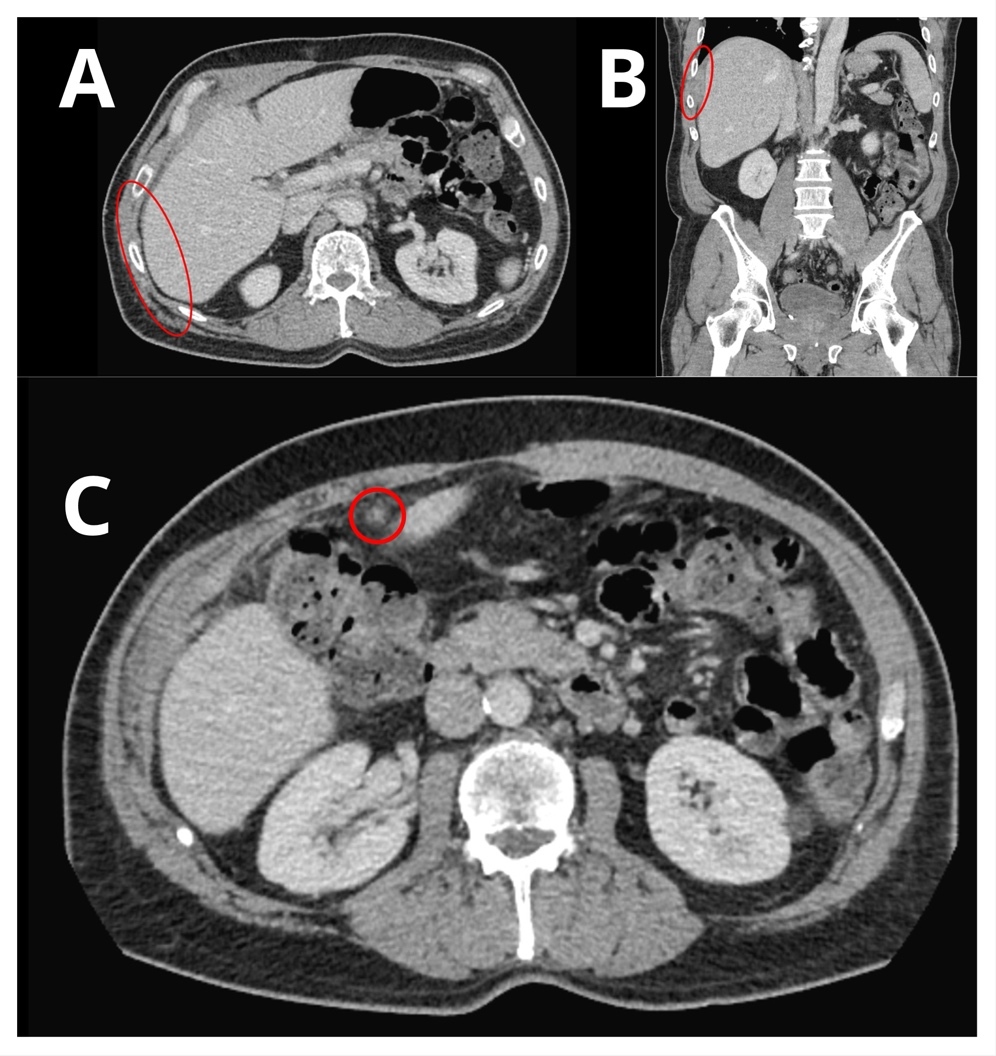

A computer tomography (CT) scan of the abdomen and pelvis was performed and showed nodularity along the right hemidiaphragm, soft tissue nodularity within the peritoneum, nodular soft tissue along inferior mesenteric and superior rectal distribution, and indistinct areas of enhancement deep to right ventral abdominal wall concerning for peritoneal metastases (Figure 2). A positron emission tomography (PET) scan showed multifocal FDG-avid peritoneal lesions suspicious of metastatic disease of uncertain primary origin (Figure 3). Image-guided biopsies (CT- and ultrasound-guided) from the right upper and lower quadrants revealed only fibroinflammatory tissue, with negative microbiologic and cytologic results. Tumor markers (CA19-9, CA125, AFP, CEA, β-hCG) were within normal limits.

Radiologic differentiation is challenging. DGs located around the liver and in peritoneum may be mistaken for peritoneal metastatic implants or enlarged lymph nodes, as they often appear as round soft-tissue nodules with a high-attenuation peripheral rim on contrast-enhanced CT.2 Unenhanced CT can be helpful in revealing the calcified nature of these nodules, supporting the diagnosis of DGs.2 However, the presence of calcification is not entirely specific, as mucin-producing tumors may also contain areas of calcium deposition. Therefore, imaging must always be interpreted in the context of clinical history and prior surgical procedures.

Radiologically, these lesions often appear as heterogeneous soft-tissue masses or rim-enhancing collections that can be mistaken for malignancy.9 The presence of small, calcified foci within lesions may suggest gallstones; however, radiolucent stones can be missed, complicating diagnosis. PET scanning can further mislead clinicians by showing FDG uptake in inflammatory tissue, as occurred in this case, prompting extensive workup for cancer of unknown primary.